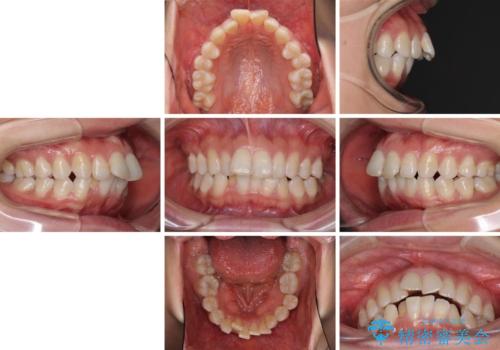

- 上の前歯の飛び出した感じと上下前歯のデコボコを気にして来院された患者様です。

叢生が強く、口元の突出感もあるため、上顎左右第一小臼歯4本を抜歯することとしました。

2年ほどインビザラインを使用しましたが、どうしても歯の移動がマウスピースに追随せず、全顎ワイヤー矯正へ切り替えました。

ワイヤー装着後は2年弱で、しっかりと仕上げることができました。